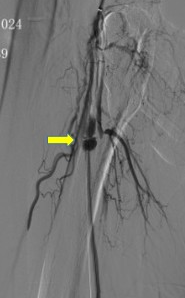

1、左股动穿刺置入猪尾导管造影双髂动脉及右下肢动脉,造影见右股浅动脉长段闭塞,腘动脉显影尚可,膝下胫前动脉显影,胫后及腓动脉未显影。

4.进一步造影见右股浅动脉近端瘤样扩张,伴局部造影剂滞留现象。

医疗组再次调阅术前CTA影像横断面:右股浅近端此区域存在血管扩张样改变(见下图)